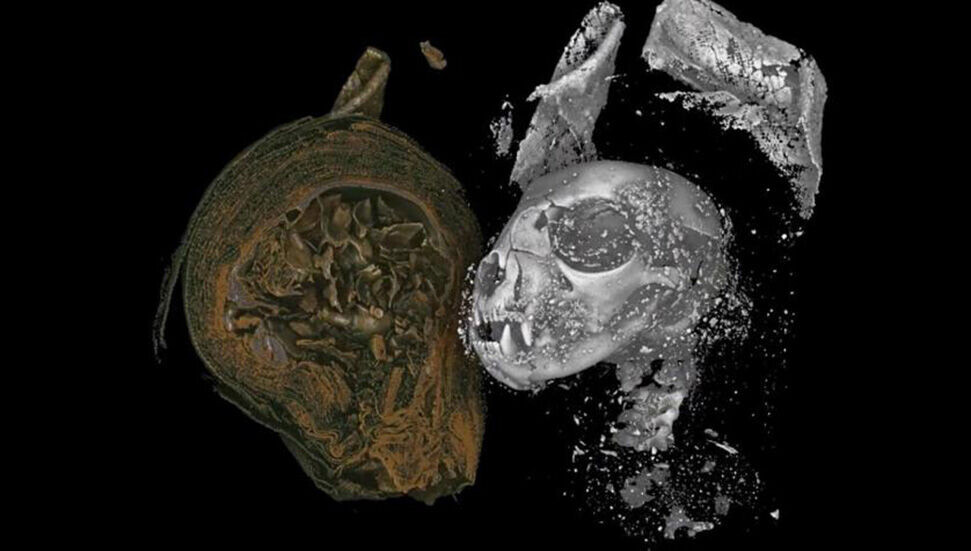

Mesaj, aynı dergide geçen Ağustos ayında yayınlanan bir araştırmayla ilgili notları da içeriyordu. Söz konusu mesajda, insan mumyalarında virüsü aramaya katılan Mısırlı-Amerikalı bir araştırma ekibi tarafından ileri sürülen, “maymun çiçeği” virüsünün hayvan kökenli olduğu ve daha sonra evrimleşerek insanları enfekte ettiği fikrine yer verilmişti. Zira çiçek hastalığı yalnızca insanlara özgü bir patojen olup hayvanlara bulaşmazken maymun çiçeği, hayvan kökenli bir hastalık. Bu nedenle zoonotik bir virüs ararken yapılacak ilk şey hayvan mumyalarına yönelmek. Araştırmacılar, yayınladıkları mesajlarında, Kaliforniya Üniversitesi Çevre ve Sürdürülebilirlik Enstitüsü'ndeki Tropikal Araştırma Merkezi'nden bir araştırma ekibinin, Afrika sincabının tarihi örneklerinde virüsün genetik materyalini bulduğunu belirttiler. Çalışmada virüsün genetik materyalinin insan mumyalarında bulunmasının muhtemel olduğunu öne sürmek için kullanılan bu araştırma, hayvan mumyalarının böyle bir araştırma çabası için en önemli seçenek olabileceği görüşünü desteklemekte.

Kaliforniya Üniversitesi Çevre ve Sürdürülebilirlik Enstitüsü Tropikal Araştırma Merkezi'nden araştırma ekibi, 1899 yılına ait Afrika sincabının (Funisciurus sp) yaklaşık bin müze örneğini inceledi ve bazılarında genetik “maymun çiçeği” virüsüne rastladı. Bu sonuç araştırmacıları, 1958'de ilk kez duyurulmadan önce insanlarda ve hayvanlarda "maymun çiçeği" virüsünün bulunduğunu söylemeye sevk etti.

Avustralya'daki Flinders Üniversitesi Arkeoloji Fakültesi'nden ve İtalya'daki Fabab Araştırma Merkezi'nden Francesco Maria Galassi, mesajda belirtilenlere katıldığını söyledi. Galassi, Şarku’l Avsat’a yaptığı açıklamalarda şu ifadelere yer verdi: “Binlerce yıllık örneklerden, özellikle de "DNA" tipindeyse, genetik materyalin elde edilmesini sağlayan modern teknikler, hayvan mumyalarını araştırma için zengin bir materyal haline getiriyor.”

"Maymun çiçeği" virüsü, "DNA" genetik materyaline sahip. Bu nedenle mumyalanmış herhangi bir hayvanın enfeksiyon kapması durumunda, o genetik materyal modern teknikler kullanılarak geri kazanılabilir.